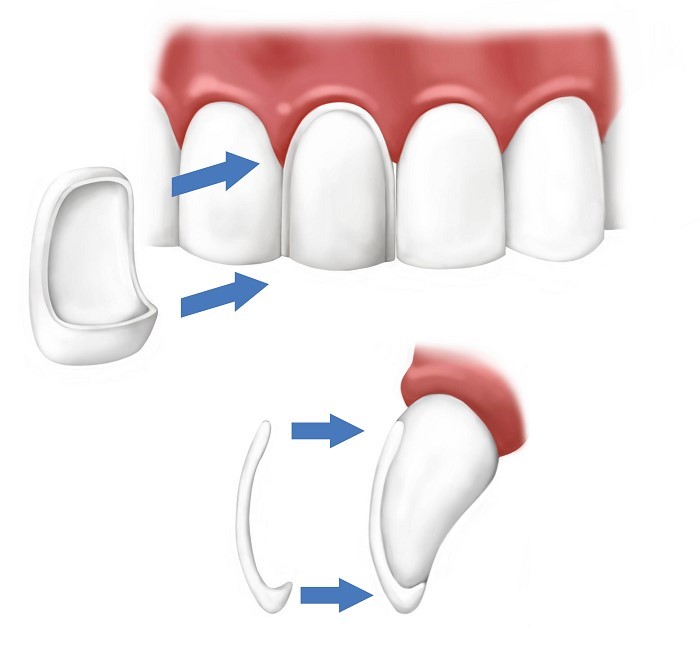

روکش دندان نوعی روش مراقبتی دندانپزشکی می باشد که دندانپزشکان برای محافظت بیشتر دندان از آن استفاده می کنند. در واقع روکش دندان نوعی کلاهک می باشد که پس از قالب گیری، متناسب با سایز دندان شما ساخته می شود و بر روی تاج دندان تان قرار می گیرد. جنس روکش دندان می تواند از سرامیک، فلز یا حتی ترکیبی از سرامیک و فلز باشد. روکش های سرامیکی به روکش های ایمکس و روکش های زیرکونیا معروف هستند. روکش های تمام فلزی معمولا از جنس طلا یا نقره می باشند. روکش های pfm یا ترکیبی معمولا در قسمت وسطشان آلیاژ فلز قرار دارد و اطراف آن را چینی ( پرسلن) محاصره کرده است.

دندان هایی که آسیب جدی دیده اند و با پر کردن مشکل آن ها حل نمی شود، نیاز به روکش دارند. تشخیص این موضوع بر عهده دندانپزشک شماست. به هنگام مراجعه به دندانپزشکی، با معاینه ای ساده دندانپزشک تشخیص می دهد که برای دندان آسیب دیده شما روکش قرار دهد یا خیر؛ اما اگر نیاز به روکش باشد، همان ابتدا روکشی متناسب با دندان شما وجود ندارد. دندانپزشک باید مراحلی را بر روی دندان انجام دهد و سایز دندان تان را برای لابراتور بفرستد و سپس مراحل روکش گذاری را انجام دهد.

مراحل روکش گذاری دندان شامل موارد ذیل می باشد:

- در اولین مرحله دندانپزشک شما با توجه به ضخامت روکشی که انتخاب شده، دندان شما را می تراشد.

- بر روی دندانی که تراش خورده است قالب گیری انجام می شود. در همین مرحله رنگ قالبی که متناسب با دندان های شما باشد انتخاب می شود.

- گاهی اوقات به عنوان تست از فریم فلزی یا زیرکونیا استفاده می شود.

- برخی موارد نیز روکشی از جنس پرسلن بر روی دهان فرد امتحان می شود.

- در آخرین مرحله روکش نهایی بر روی دندان نصب می شود و از آن پس فرد می تواند لبخندی زیباتر را به دیگران هدیه دهد.